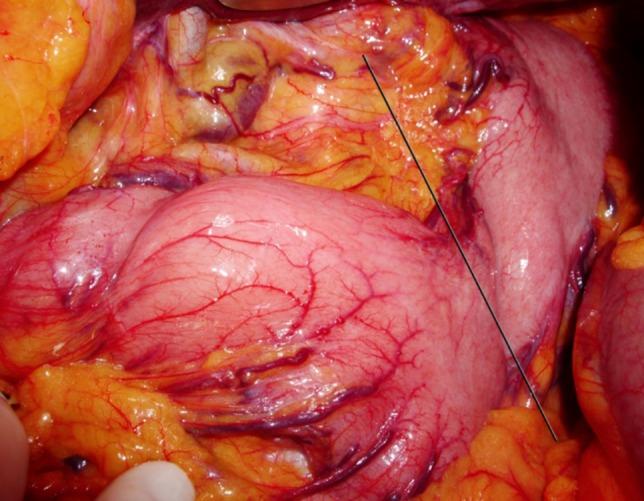

原发性胃扭转:两例报告。

Primary gastric volvulus: a report of two cases.

Gastric volvulus is an uncommon cause of gastric obstruction. It can be classified as primary when no underlying condition is identified as the cause for the rotation. An acute presentation includes typical symptoms and is frequently detected by imaging studies. Chronic cases present with intermittent vague symptoms and imaging studies may be normal during the symptomatic interval. The lack of specific symptoms and signs delays the diagnosis of chronic volvulus. However, appropriate treatment demands prompt diagnosis. We report two cases of primary gastric volvulus, with chronic or subacute symptoms and normal imaging studies during the asymptomatic periods. Both were treated surgically and had an uneventful follow-up.

摘要

胃扭转是胃梗阻的一种罕见原因。当未发现潜在病因导致胃扭转时,可将其归类为原发性。急性表现包括典型症状,常通过影像学检查发现。慢性病例表现为间歇性模糊症状,在症状发作期间影像学检查可能正常。缺乏特异性症状和体征会延迟慢性胃扭转的诊断。然而,恰当的治疗需要及时诊断。我们报告两例原发性胃扭转病例,均有慢性或亚急性症状,且在无症状期影像学检查正常。两例均接受了手术治疗,术后随访情况良好。